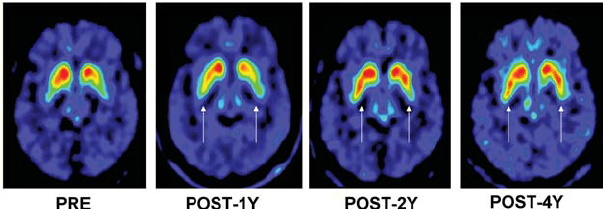

Following the meeting with Giovanna to review the first version of the FDOPA PET Imaging leaflet, Gill worked on the revisions needed to create the second version. Giovanna had provided three different photographic images of PET scans:

Gill experimented with drawing the rainbow colour-scheme and the blue-green colour scheme PET scans, as the red colour scheme is not as visually appealing and would not work as well with the existing illustrations. The scans will have to be placed on a black background (as in the header image of this post) to look their best, and to match how the scan results appear in the PET imaging software.